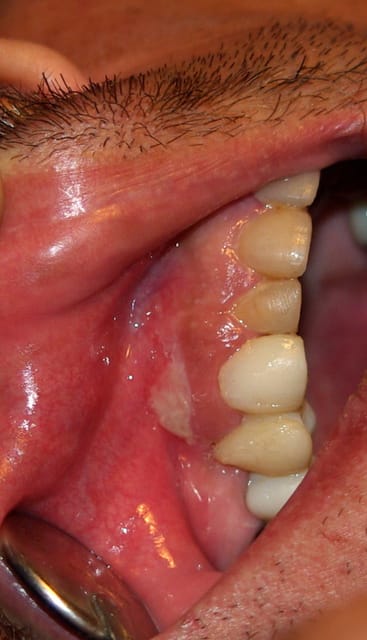

Le patient se plaint de douleurs gingivales en regard de la 13 depuis 24h. Elles sont permanentes, irradiantes, insomniantes et ne cèdent pas aux antalgiques. Elles s'accompagnent d'une altération de l'état général: grosse fatigue voire désorientation mais sans fièvre ni adénopathie.

La lésion semble bulleuse devenant érosive érythémateuse recouverte des lambeaux persistants blanchâtres du toit de la bulle. De taille environ 1cm de diamètre. Entourée au départ de petites bulles transparentes encore intactes.

atteinte virale, zona en 1 ou herpès why not ?? car AEG associé et lésion vésiculeuses d'après la description car les photos ne sont pas très parlante.

J'ai revu le patient aujourd'hui, l'état général est amélioré mais les douleurs n'ont pas diminué limitant l'alimentation. La lésion ne semble plus être vésiculeuse, elle forme un placard blanchâtre sur un fond érythémateux mais le raclage est rendu difficile car très douloureux, je pensais à une candidose mais la couche blanchâtre ne semble pas s'éliminer et la lésion est isolée et ne semble pas s'étendre.

En même temps l'aspect me ferait bien penser à un lichen...